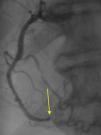

The authors present the case of an 83-year-old male with a history of hypertension, appendectomy and cervical spine surgery who presented at the emergency department with epigastric pain and dyspnea at rest for six hours. The physical examination was compatible with refractory acute pulmonary edema requiring endotracheal intubation and ventilation. The electrocardiogram showed sinus rhythm with ST-segment elevation in the inferior leads. The emergent coronary angiography revealed three-vessel disease with distal occlusion of the right coronary artery (Figure 1, Videos 1 and 2). Primary angioplasty was performed successfully (Figure 2, Video 3). During the procedure a contrast retention image was observed apparently synchronous with the cardiac/respiratory cycle (Figure 3, Video 4). The first possibility that came to mind was an aortic dissection, which was excluded by an anteroposterior projection, which showed that the image was in the midline (Figure 4, Videos 5 and 6). A chest computed tomography scan was then requested to rule out the presence of a fistula (esophageal or bronchial), which revealed that the image corresponded to retention of contrast in the medullary canal from myelography performed in the 1980s (Figure 5A and B).